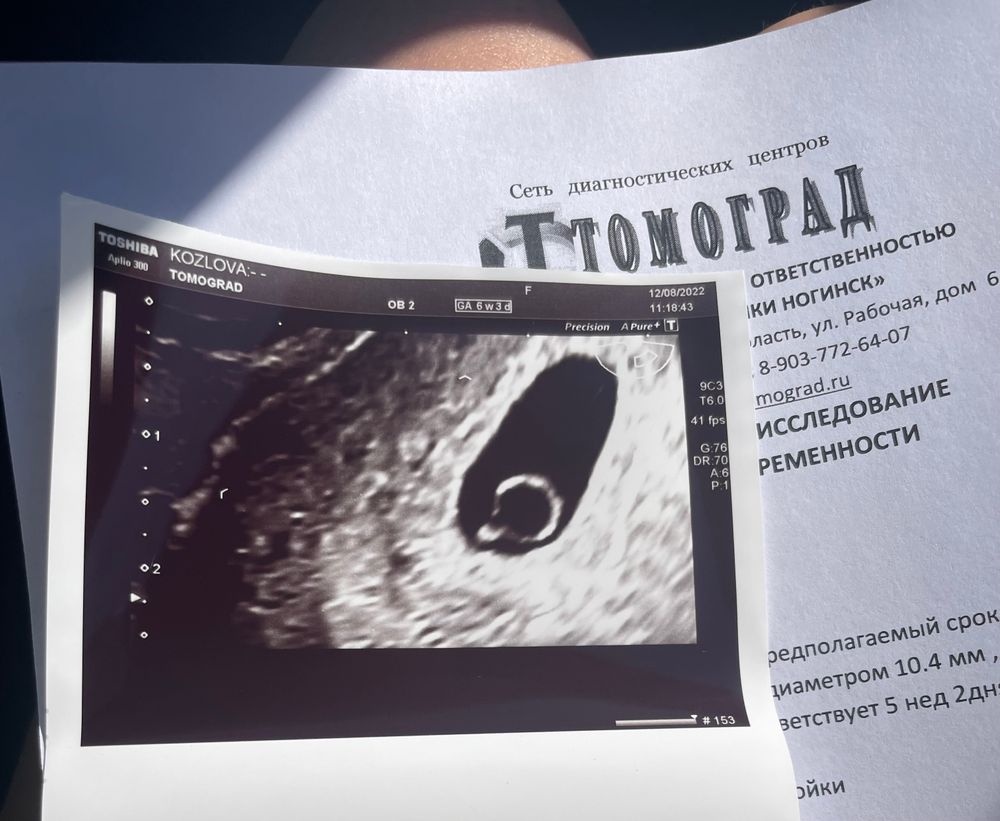

Наше первое узи 💞

Надо же, вы снова в положении) поздравляю) Вообще по моему ктр как раз по сроку. У меня оба малыша были 2.5 мм ровно на 5.6 недель. Это было на экспертном аппарате у очень хорошего врача А у вас 4.4. Это как раз на 6.1.

Ромашка, может нормы в моей клинике другие 🤷‍♀️ но главное что все хорошо и сердечко пульсирует 🙏🏻

Анастасия, это точно) Но по всем табл 5.6-6.2 у вас есть)